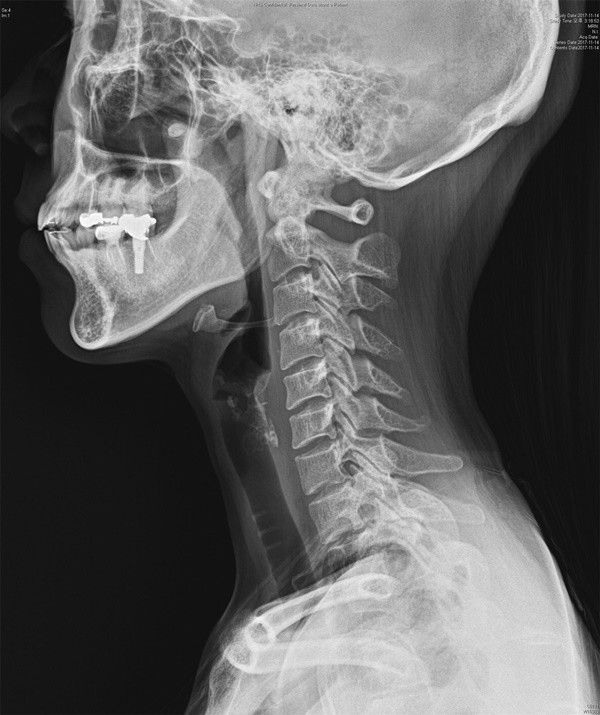

일자목증후군이란 앞으로 목을 길게 빼는 자세 때문에 정상적인 경추만곡인 C자 형태의 경추 정렬이 소실돼 생기는 증상을 가리킨다. 증상으로는 경항통(목 통증), 견비통(어깨와 팔 부위가 아픈 증상), 수지(손가락) 저림, 두통, 만성피로, 어지럼증, 안구 피로 등이 나타난다.